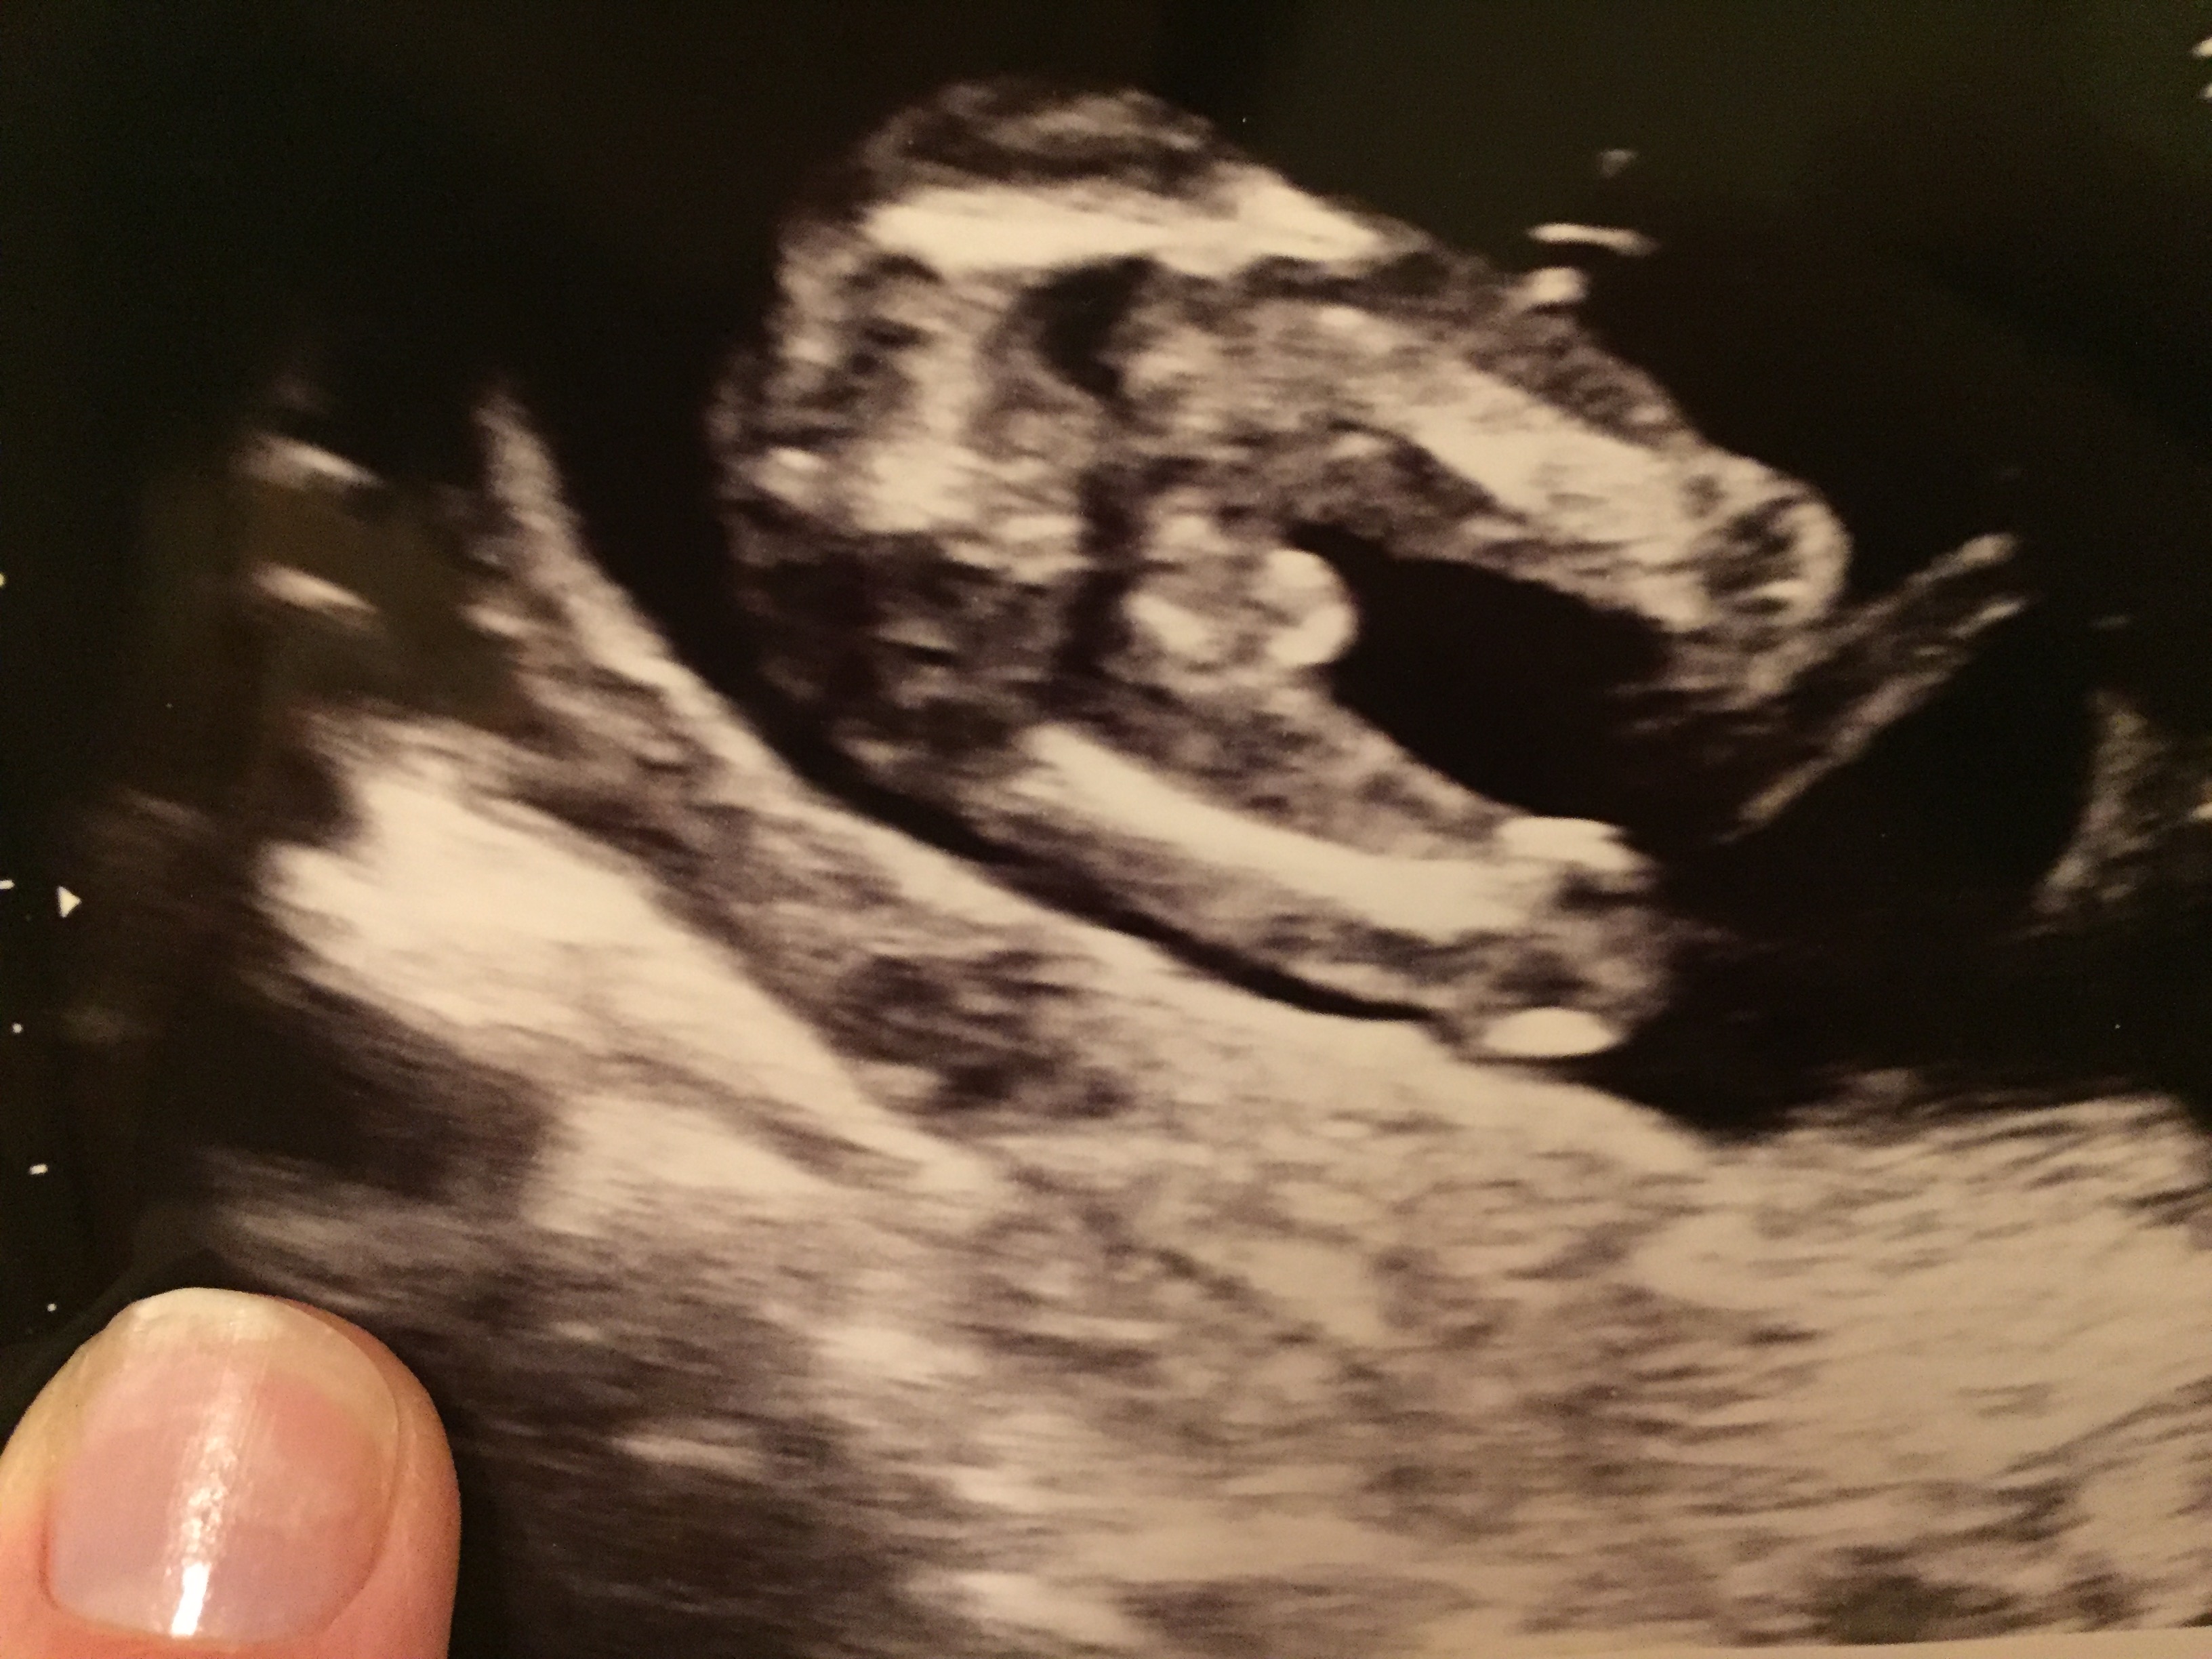

15+6 or 16+1 depending on which medical professional I'm talking to

Is this definitely boy? No chance of it being just swollen girl parts....?

I'm pretty sure that's a boy :) More pics?

Boy, sorry sounds like you wanted to hear girl. I know how that feels! Good luck!

Yep, all boy for sure. No doubt. Sorry you didn't hear girl hun.

I'm sorry, I do think he looks boy. Congratulations on a new little guy.

Thanks, it was confirmed again this week. He is lovely, even a cutie on his scan.

Well, not to get false hopes up because I do think it's a boy but there was just a gal (I think her user name was "it takes 3" or something like that, her post was titled "is tech wrong" and there was a poll in it) who had a very similar looking potty shot and found out it was a girl a few weeks later.

If your nub hadn't been so girly I would not mention this at all because I don't want to give you false hope but seriously, her pic looked very much like yours and your nub was quite girly, CD